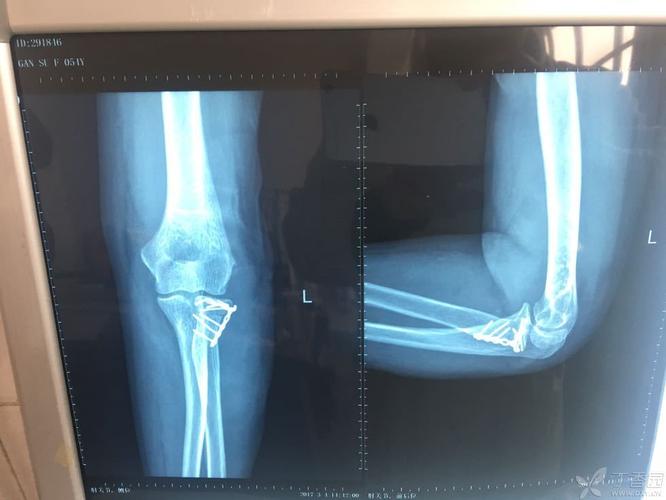

桡骨小头手术入路,桡骨头骨折手术入路图

桡骨头骨折手术入路图

桡骨小头骨折图片

桡骨小头骨折手术图谱

桡骨小头骨折

桡骨头骨折